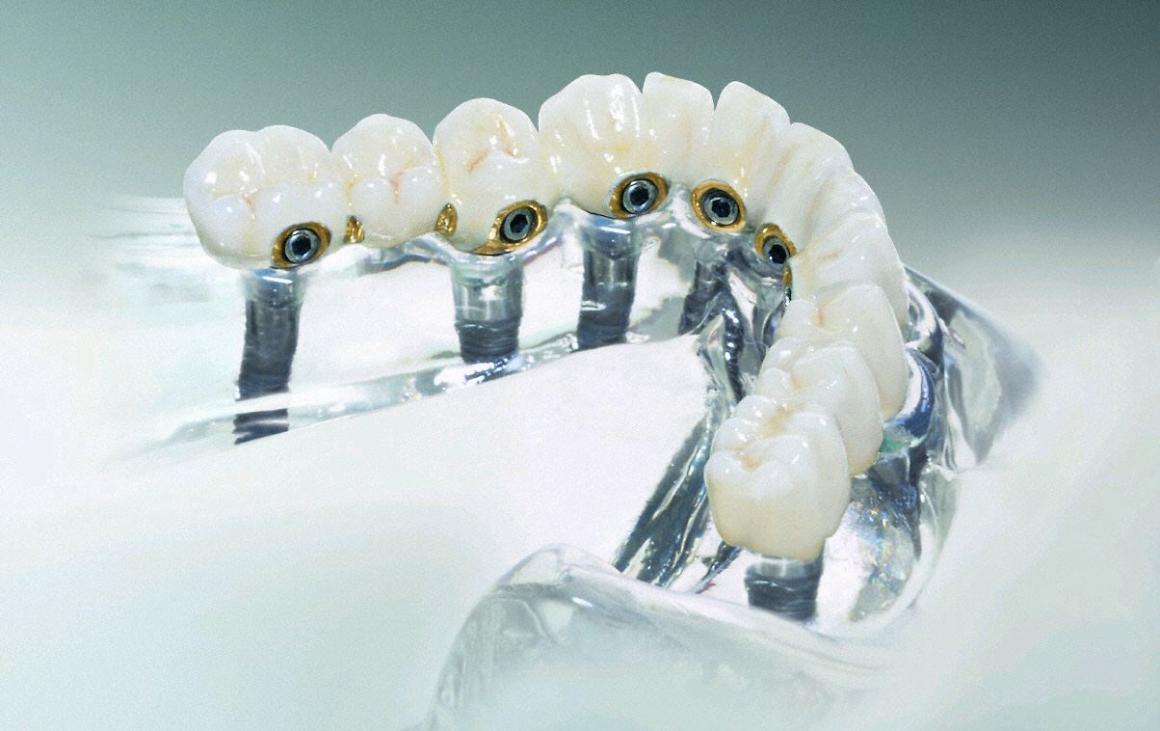

Feste Brücke im zahnlosen Kiefer

Bei ausreichender Knochenstärke können Implantate als Brückenpfeiler bis in den Molarbereich gesetzt werden. Bei weniger Knochen enden die Implantatpfeiler weiter vorn. Eine "Extensionsbrücke" ist die Alternative.